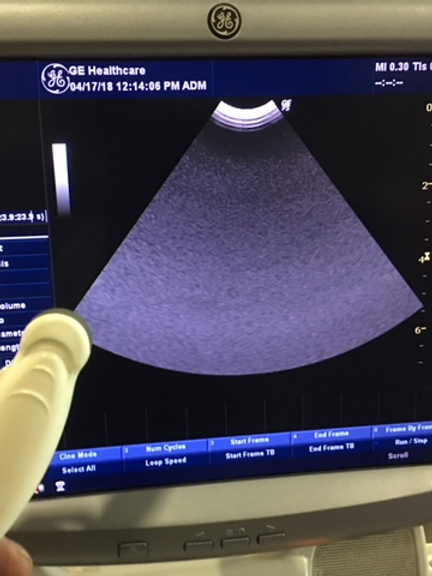

Unrivaled Imaging Capability: From gynaecology/obstetrics to urology, cardiology, and paediatrics, the LOGIQ P5 delivers exceptional 3D/4D imaging across a range of medical specialties. With its advanced features, it stands as the most powerful system in its price range, offering unmatched diagnostic precision and clarity.

Enhanced Functionality: Equipped with a 15-inch TFT LCD monitor and a flexible monitor arm, the LOGIQ P5 ensures optimal viewing comfort and convenience during procedures. With a spacious 50 GB hard disk for image storage and directional power Doppler imaging, it meets the demands of modern healthcare settings.

Effortless Optimization: Streamline your workflow with automatic tissue optimization, coded harmonic imaging, and high pulse repetition rate capabilities. The LOGIQ P5 is designed to enhance efficiency and accuracy, empowering healthcare professionals to focus on patient care.

- Directional power Doppler imaging for detailed vascular assessments

- Automatic tissue optimization and coded harmonic imaging for enhanced image quality

- High pulse repetition rate for improved diagnostic accuracy